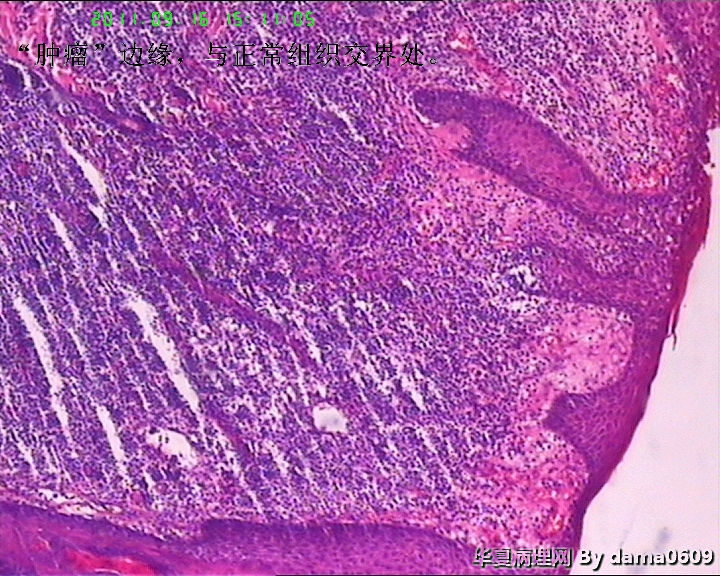

女,背部皮肤肿物,病史不详。送检梭皮组织一块,S:4.5x2.2cm,正中一圆形隆起,直径2.0cm,表面黄白色与周围界清,切面实性灰白色。

• 背部肿物,急请老师看看!!图1

图1